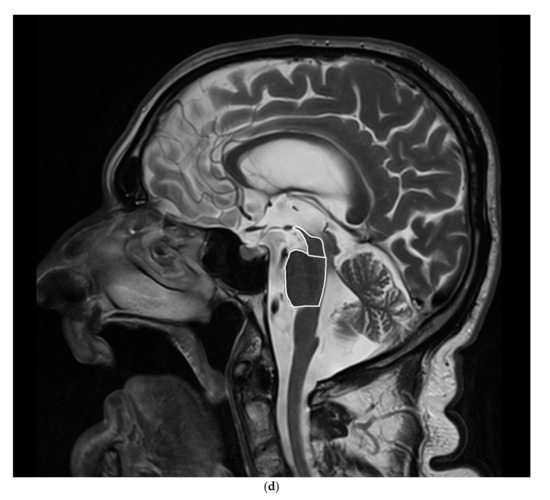

5.1.2. MRI

There was a significantly smaller midbrain surface in patients with PSP-P in comparison with patients with MSA–P, 0.76 cm2 vs. 1.08 cm2. Moreover, the ratio of midbrain to pons (M/P ratio) was also significantly smaller in patients with PSP-P vs. MSA-P 0.16 vs. 0.23, but the MRPI values were higher in patients with PSP-P vs. MSA-P 18.75 vs. 10.6 (Table 1 and Table 2) (Figure 1a–d).

Figure 1.

(a). Scatterplot presenting the significant differences between MSA-P and PSP-P in the midbrain surface, (b) Scatterplot presenting the significant differences between MSA-P and PSP-P in the M/P ratio, (c) Scatterplot presenting the significant differences between MSA-P and PSP-P in the MRPI, (d) The atrophy of the mesencephalon in the MRI of a patient with PSP-P.